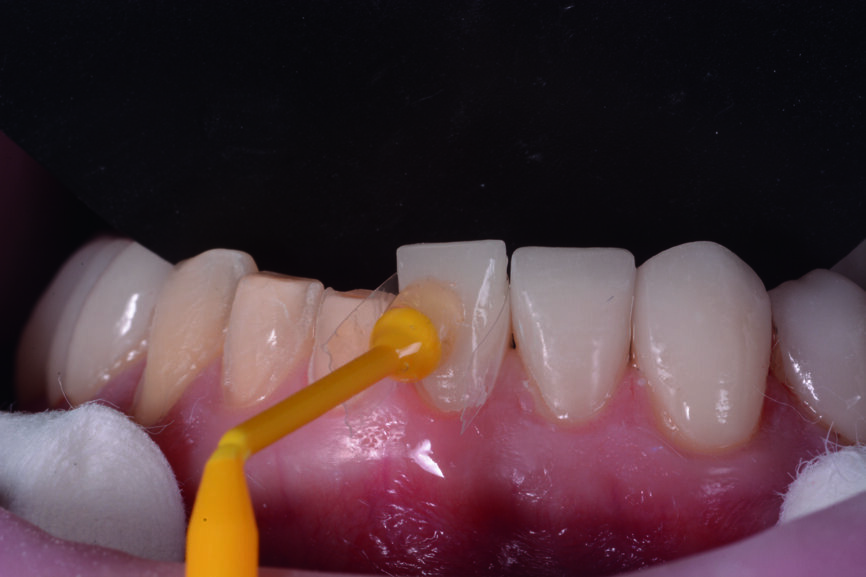

Figs. 11 et 12 : Les couronnes (11–13 et 21–23) et les facettes (14–17, 24–27, 31–37 et 41–47) sont collées sur les dents piliers avec une colle composite photopolymérisable (Futurabond U et Bifix QM).

Les facettes et les couronnes définitives sont conçues numériquement par le logiciel de conception Ceramill Mind (Amann Girrbach) et produites dans une unité d’usinage (Ceramill Motion 2, Amann Girrbach) à partir de blocs de céramique au disilicate de lithium (VITABLOCS TriLuxe forte, fabriqués par VITA Zahnfabrik H. Rauter & Co. KG, et adaptés à l’usinage dans Ceramill Motion 2, Amann Girrbach; Fig. 10). Après une insertion d’essai pour confirmer la qualité du joint marginal et des propriétés optiques, un écarteur labial et jugal (OptraGate, Ivoclar Vivadent) est mis en place dans la bouche du patient.

Les dents piliers, les facettes et les couronnes en céramique sont préparées selon les recommandations du fabricant : la surface de la céramique est sablée avec des particules d’oxyde d’aluminium de 50 μm et mordancée durant 20 secondes à l’acide fluorhydrique à 5 %. Elle est ensuite rincée 20 secondes avant d’être traitée à l’acide phosphorique à 37 % (Total Etch, Ivoclar Vivadent) et à l’alcool à 96 % pour la nettoyer. Pour terminer, elle est conditionnée 20 secondes avec du silane (Monobond Plus, Ivoclar Vivadent).

Les couronnes (#11–13 et 21–23) et les facettes (#14–17, 24–27, 31–37 et 41–47) sont collées sur les dents piliers au moyen d’une colle composite photopolymérisable (Futurabond U et Bifix QM, VOCO). Un dispositif équipé d’une lampe LED à haute puissance (Celalux 3, VOCO) est utilisé pour la photopolymérisation (Figs. 11 et 12).